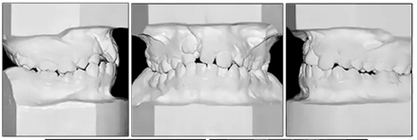

咬合關(guān)系:右側(cè)磨牙有II類關(guān)系傾向,尖牙關(guān)系II類;左側(cè)磨牙關(guān)系完全I(xiàn)I類,尖牙關(guān)系I類。上頜雙側(cè)反合,中線稍有偏離。覆合、覆蓋減少。上頜中切牙向腭裂側(cè)旋轉(zhuǎn),上頜右側(cè)尖牙頰側(cè)異位萌出,雙側(cè)乳尖牙仍存在?;颊呱项M弓嚴(yán)重?fù)頂D(擁擠度約10mm),下頜弓輕度擁擠4mm(擁擠度約4mm)(圖1 ;圖2)。牙周檢查良好。